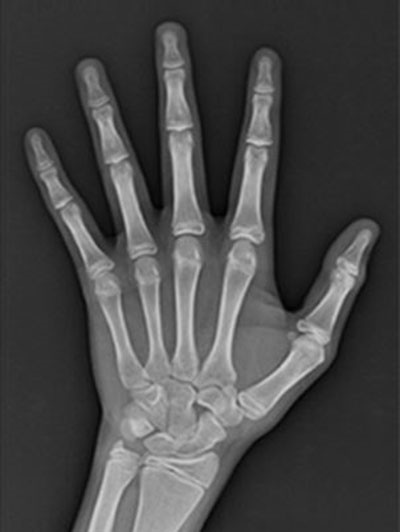

![연세굿데이치과] 성장판 검사가 중요한 이유 관련 이미지 2](https://pub-9f2bb3498faf4d1d8714b41df24753e3.r2.dev/content/clinics/archive/5hurea2jnb/naver_blog/eunkyo3370/assets/by_hash/e95672fd1edbaef49d104e178fe66272de0de7392d580faed610c06bb14c9ae3.jpg)

(좌)19세 성장판, (우)5세 성장판

(열린 성장판)

(닫힌 성장판)

성장판은 뼈의 끝부분에 있는 연골조직인데요.

성장기에는 연골세포가 분화하여 키가 자라지만

사춘기에 접어들면 뼈성숙이 빨라지면서

연골이 딱딱한 뼈로 바뀌어 성장판이 닫히게 됩니다.

아이들마다 성장속도가 전부 다르기 때문에

성장판 검사를 통하여 ‘적절한 치료시기’를

미리 진단받으시는 것을 권유드립니다 :)